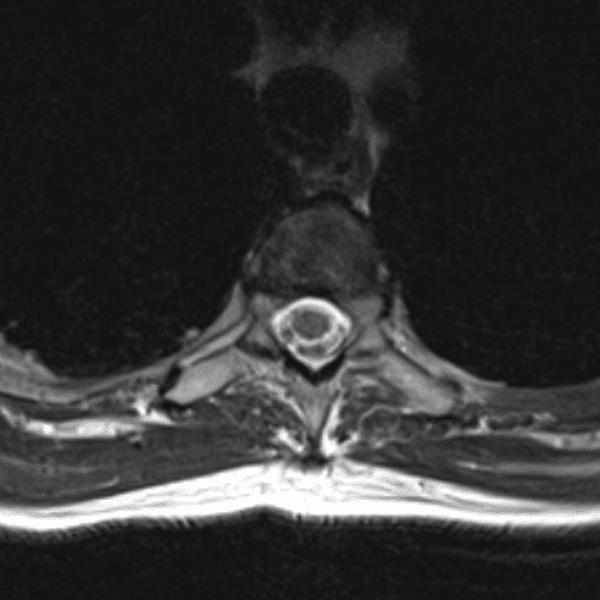

Simulates call by including subtle or difficult cases and some normals.

35 cases